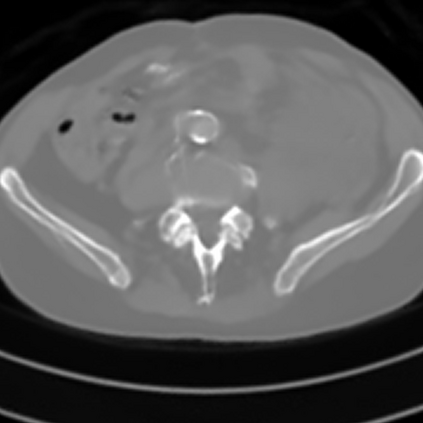

Sparse-view computed tomography (CT) -- using a small number of projections for tomographic reconstruction -- enables much lower radiation dose to patients and accelerated data acquisition. The reconstructed images, however, suffer from strong artifacts, greatly limiting their diagnostic value. Current trends for sparse-view CT turn to the raw data for better information recovery. The resultant dual-domain methods, nonetheless, suffer from secondary artifacts, especially in ultra-sparse view scenarios, and their generalization to other scanners/protocols is greatly limited. A crucial question arises: have the image post-processing methods reached the limit? Our answer is not yet. In this paper, we stick to image post-processing methods due to great flexibility and propose global representation (GloRe) distillation framework for sparse-view CT, termed GloReDi. First, we propose to learn GloRe with Fourier convolution, so each element in GloRe has an image-wide receptive field. Second, unlike methods that only use the full-view images for supervision, we propose to distill GloRe from intermediate-view reconstructed images that are readily available but not explored in previous literature. The success of GloRe distillation is attributed to two key components: representation directional distillation to align the GloRe directions, and band-pass-specific contrastive distillation to gain clinically important details. Extensive experiments demonstrate the superiority of the proposed GloReDi over the state-of-the-art methods, including dual-domain ones. The source code is available at https://github.com/longzilicart/GloReDi.